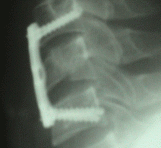

27-MARCH-2007 ALAA NAEEM RADWAN 28 YEARS FLEXION FRACTURE OF C5.

The patient was transferred from another hospital with history of falling down three days ago, during diving, during what he got flexion facture of the C5.

MRI cervical spine performed 26-March-2007 showing the fracture of C5 without disc prolapse and intact spinal cord.

On examination: the patient is neurologically free with collar and cut wound of the scalp in the forehead. There is slight weakness both legs. Considering that the fracture is an unstable one, reduction and stabilization was suggested.

Discectomy of C4-5 was performed to secure the process of reduction with distraction, using the Hallo ring with 8 Kg applied with slight hyperextension. Using three level 24 mm length Stryker cervical miniplate, fusion of C4-6 with 18 mm screws applied with divergent angulations, to aid the distraction and consequently the reduction. The most difficult part of surgery was to insert the construct to the intended site, due to small incision. Several check X-rays demonstrated good alignment and reduction of the bony structures.

Routine closure of the wound and smooth postoperative recovery with improvement of the motor power both feet.

Check X-ray 6 hours after surgery after ambulation of the patient.

Considering that the fracture is an unstable one and cannot stand load with severe angulations and decrease of the anterior height of the body of C5 less than 10% than normal, reduction and fusion of the fracture one level above and one level below must be done.

To avoid slippage of the fractured C5 during reduction and fixation, discectomy of C4-5 was performed and the body of C5 was left without screwing to prevent such possible complication. This was done with visual control through the discectomy site.